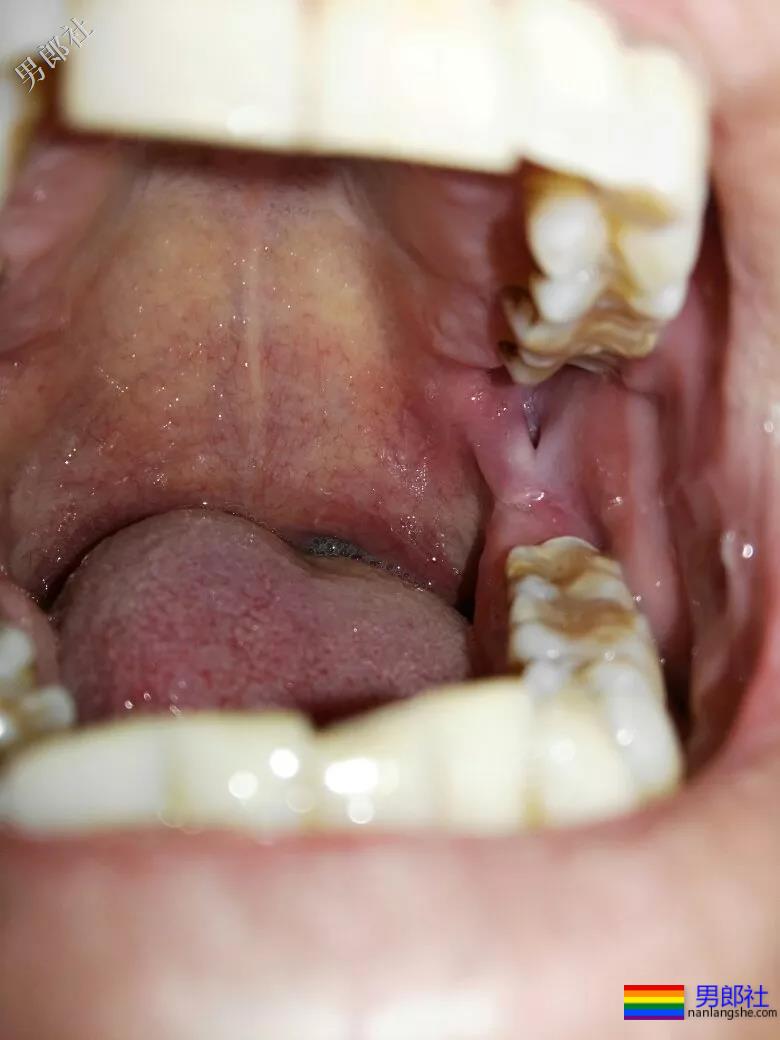

庄老因为包皮过长,且西北地区缺水,从来没有翻开清洗的习惯,即便到了北京也如此。伴随着无数次公厕鸟洞中被口的经历,他的包皮之下开始发炎。

随后,他购买了各种硫磺皂,但无论怎么清洗都没改善,异味也越来越严重。同时私密处还长了不少红色斑点,逐渐粘结成一整块。

恐惧犹如洪水一般倾覆进庄老心里,终于下定决心去了趟医院。检查结果让他当场吓懵,“阴茎癌”。在东拼西凑了手术费之后,庄老切去了自己欲望的四厘米。

“要不是口腔溃疡,也没事。”

因为工地上的伙食火气大,辣口的饮食让阳哥患上了口腔溃疡。一般情况,都不当回事,买一支清口喷剂就糊弄过去。可显然对他而言,这是带有风险的。

虽然口腔性行为感染HIV概率较低,但也会感染。对待风险,不能讲究概率,而应该知晓有无。换句话说,常在河边走哪有不湿鞋。

在前年,阳哥检查出了阳性,回家和媳妇同床回回都得戴着两层安全套,他没敢和家里人说,也不想伤害家人。